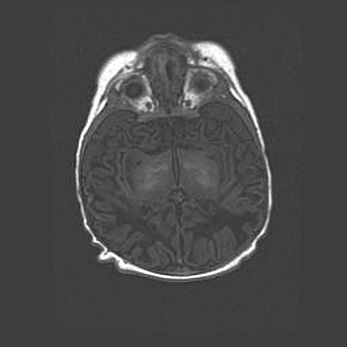

Церебральная ишемия II.

Возраст: 5 дней

Вес: 3400 г

Пол: женский

Окружность головы: 35 см

Срок гестации: 39 недель

Церебральная ишемия – это заболевание, характеризующееся недостаточностью (гипоксией) либо полным прекращением (аноксией) снабжения мозга кислородом по причине закупорки одного или нескольких сосудов. Это приводит к  что метаболическим расстройствам различной степени тяжести в тканях головного мозга, развитию коагуляционных некрозов и гибели нейронов.